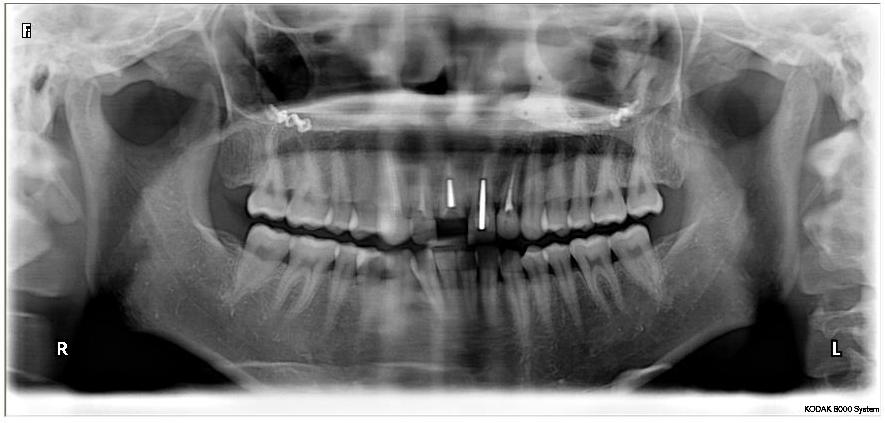

6일 성 씨는 하나투어를 통해 4박5일 신혼여행 패키지 여행상품을 290만원에 구입, 지난8월 초 필리핀 세부로 떠났다. 여행 3일차 성 씨는 잠을 자던 중 침대 모서리에 부딪혀 앞니(11번 치아)가 부러지는 상해사고를 겪었다.

성 씨는 필리핀 의료진보다는 믿을 수 있는 국내 의료진에게 치과진료를 받고자 가이드에게 경위를 입증해줄 ‘확인서’를 받은 후 서둘러 입국했다.

“현지치료를 받았다면 보험금 지급이 됐을텐데 한국에서는 비급여에 해당돼 보험혜택을 받을 수 없다”는 관계자의 설명에 그저 놀랄 수 밖에 없었다.

또 “민원인의 경우 치과치료라도 현지에서 치료받았다면 비급여대상에 속하더라도 보상이 가능할 것”이라며 "가이드가 현지치료에 대한 적절한 안내를 했다면 좋았을 것"이라고 덧붙였다.